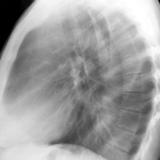

RLL Collapse  1 Lateral

Date: 02/28/2004

Views: 3183